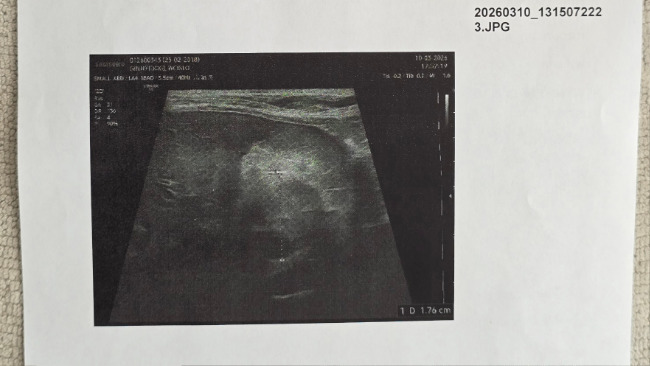

W ostatnim czasie, podczas kontrolnej wizyty Ginny u weterynarza, opiekunowie usłyszeli druzgoczącą wiadomość: guz prawego nadnercza. Potem ujawniono jeszcze nieładne nacieki na żyłę główną (CVC) i wątrobę. W dodatku dokładne zdiagnozowanie, czy guz jest operacyjny okazało się bardzo trudne.

Ginny przeszła już wiele kosztownych badań: